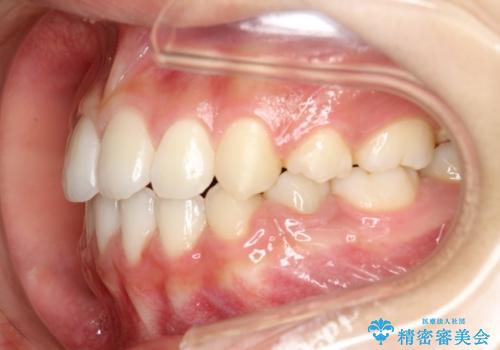

ハーフリンガル 半分裏側矯正による上下前突の抜歯矯正治療

- 20代女性

- 矯正装置

- ハーフリンガル

- 上下左右4本の第1小臼歯を抜歯する、抜歯矯正を計画した。

抜歯矯正により前歯の位置が後ろに下がり、わずかではありますが、口元に改善がみられ、歯並びもきれいに整いました。